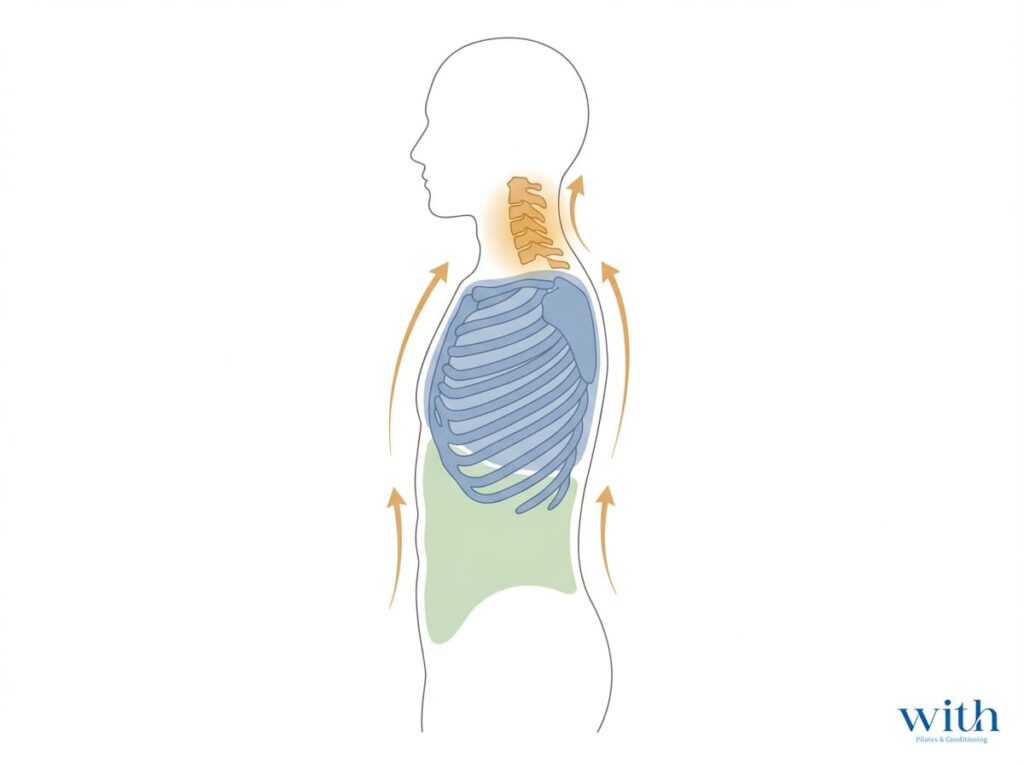

首の問題は、

- 呼吸

- 胸郭

- 体幹の安定

- 姿勢環境

といった分担構造が関与します。

なぜ鳴らしたくなるのか?(構造の問題)

多くのケースで、

- 胸郭の硬さ

- 呼吸の浅さ

- デスクワークによる前方頭位

- 体幹の支え不足

が背景にあります。

首単体ではなく、

呼吸・胸郭・体幹を含めた構造で整理することが、本質的な改善につながります。